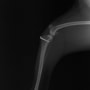

■ 症例22 ポメラニアン 1歳5か月 去勢雄

左後肢の挙上を主訴に来院した。整形学的検査、レントゲン検査より左右の膝蓋骨脱臼(左GradeⅡ〜Ⅲ、右Grade Ⅱ)を認めた。また、脛骨の前方引き出し試験の際に、引き出し兆候は認められないものの、疼痛が認められたため、前十字靭帯の損傷が疑われた。術中における、目視および関節内の操作によって、前十字靭帯の損傷や過伸展といった異常が認められなかったため、膝蓋骨脱臼の整復のみ実施した。手術手技は縫工筋及び内側広筋の解放、脛骨粗面の外側転位、滑車ブロック形造溝術、内外側関節包の縫縮を実施した。本症例は跛行もなく経過良好である。しかし、頸骨高平部の角度(TPA)が 右26.2°、左24.9°であり、解剖学的に前十字靭帯損傷のリスクが高いことから今後の経過に注意が必要である。